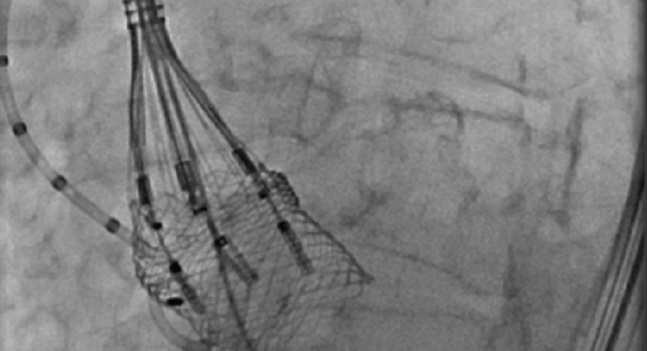

Full results of the REPRISE III trial comparing the mechanically expanded Boston Scientific’s Lotus transcatheter aortic valve replacement system to Medtronic’s self-expanding first- and second-generation valves in high-risk patients with severe aortic stenosis were published this week in JAMA.

Photo Credit: Adapted from Reardon MJ. The LOTUS TAVR System: “Cool” Case, New Technology (Including EDGE), and Clinical Program Updates . Presented at: TVT 2017. June 16, 2017. Chicago, IL.